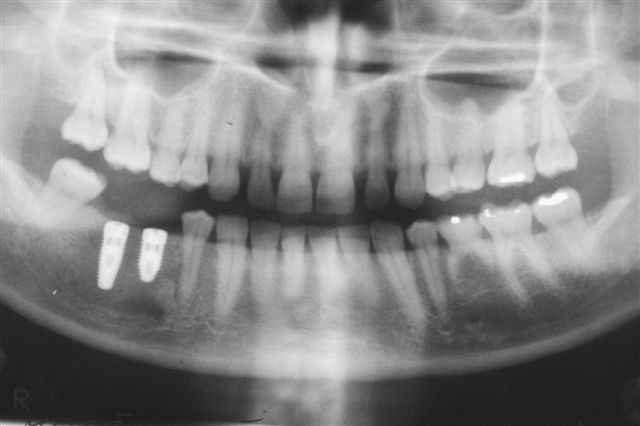

Ukázka zákroku implantace